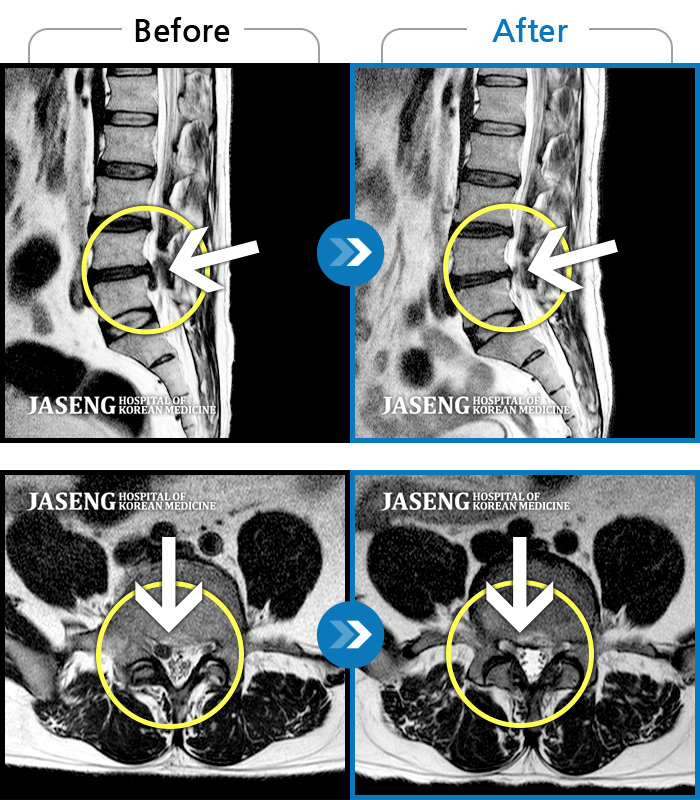

요추 추간판 탈출증을 진단받은 입원 환자의 보완대체의학 통합치료의 장기 효과

Before

After

처음 내원 시 허리 통증 및 우측 다리 저림이 심하여 일상생활이 불가능

2020.07.23 ~ 2022.08.22